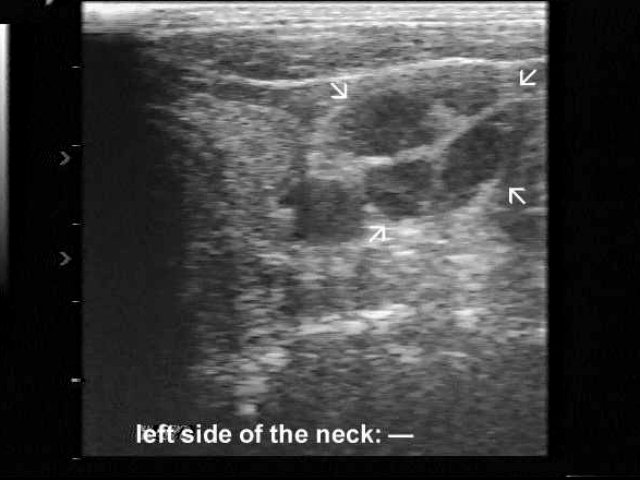

Ultrasonography. Besides the enlarged lymph nodes, US revealed a hypoechogenic lesion in the left lobe of the thyroid.